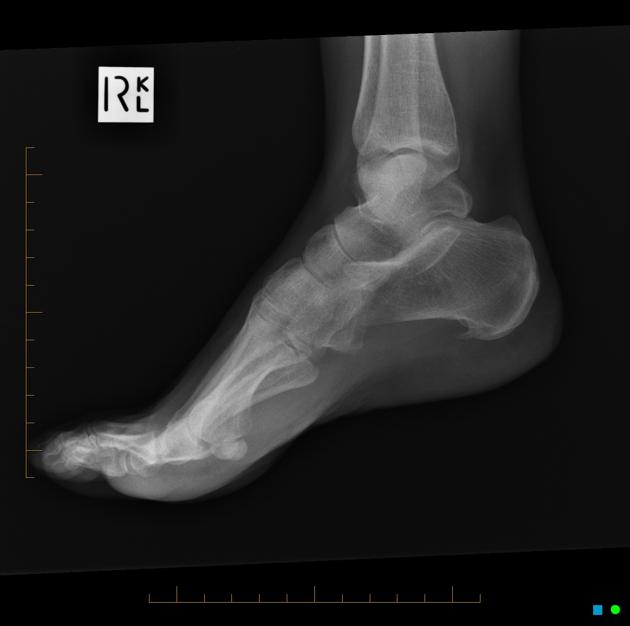

Calcaneal spur Radiology at St. Vincent's University Hospital What Is A Spur On Your Ankle Your healthcare professional gives you a physical exam. Preferred foot & ankle specialists. Bone spurs are bony growths that typically. A bone spur, also known as osteophyte, is a bony projection that forms along the edges of bones. These growths typically develop where bones meet each other in the joints. Your doctor or another member of your healthcare. Also known. What Is A Spur On Your Ankle.